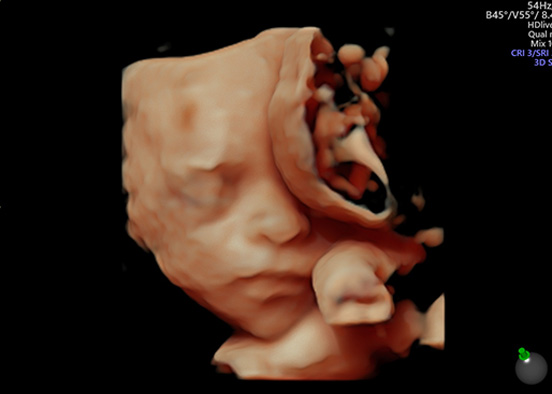

En Amal’nai ofrecemos ultrasonidos materno fetales de alta especialidad, fundamentales para cuidar el bienestar de tu bebé desde el inicio del embarazo. Cada estudio está indicado en una etapa específica y cumple con protocolos internacionales para la detección oportuna de alteraciones estructurales o cromosómicas, así como para la vigilancia del flujo sanguíneo fetal y uterino.

Este estudio se realiza en el primer trimestre y es clave para detectar posibles alteraciones cromosómicas como síndrome de Down, trisomía 18 y trisomía 13.

Además, permite estimar el riesgo combinado de alteraciones genéticas al integrar los datos del ultrasonido con análisis de sangre materna. Es una herramienta eficaz y no invasiva para embarazos de bajo o alto riesgo.

También conocido como ultrasonido anatómico, este estudio se realiza en el segundo trimestre y permite una evaluación detallada de todas las estructuras del bebé: